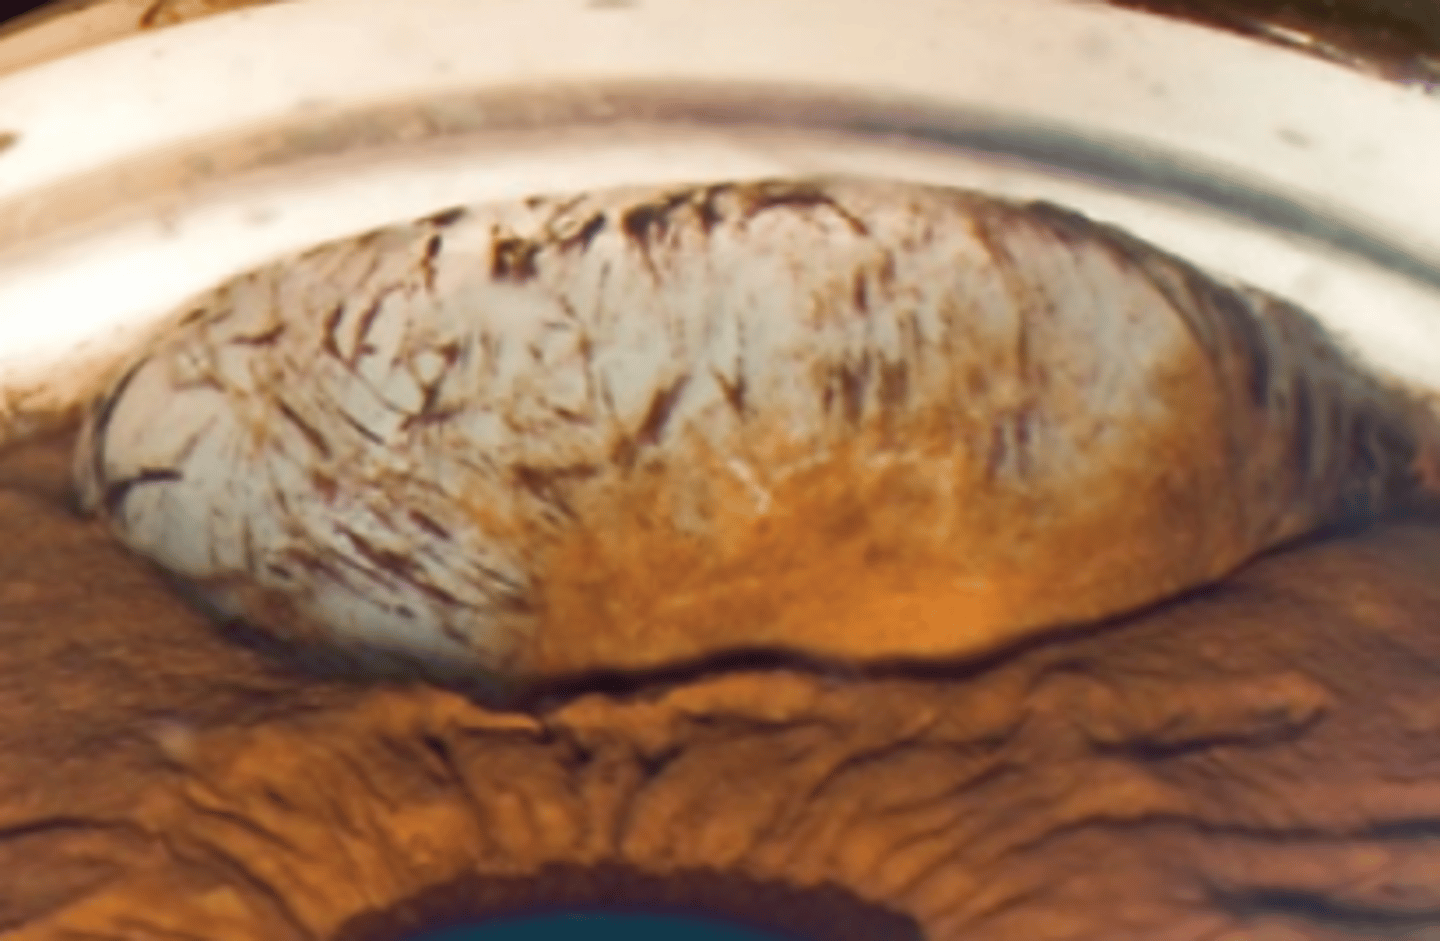

Lisch nodules

tan (varying depending on eye color) melanocytic progressive growths on the iris associated with neurofibromatosis 1.